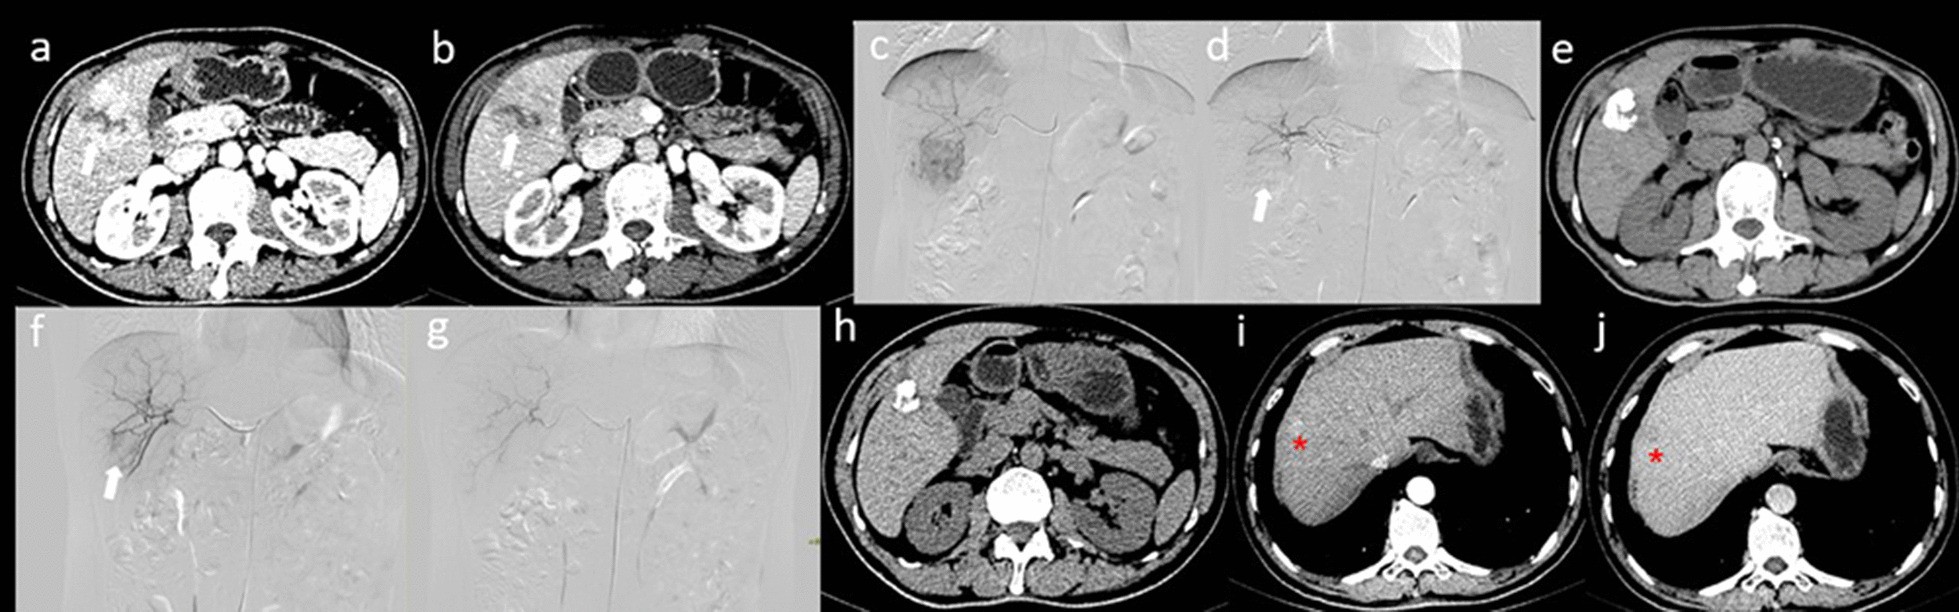

Fig. 4

CT and DSA images of a patient receiving 1 TACE treatment before combination therapy. a, b Axial CT showed a typical HCC enhancement pattern, including “wash in” in the arterial phase, “wash out” in the portal phase (white arrow) in the marginal zone, and necrotic foci in the centre. c, d DSA images before and after the initial TACE treatment; the tumour staining disappeared (white arrow). e Re-examination after one and a half months showed that the tumour had decreased in size and that viable tumours were present on the edges. f, g During the second TACE treatment, the tumour still showed staining (white arrow), indicating that the tumour blood vessels were recanalized and that the tumour was alive. The staining disappeared after treatment. h Re-examination after the combination therapy showed that the tumour had decreased in size and that there were no live foci. i, j Twelve months after late combination therapy, there was recurrence in the liver (red star sign)